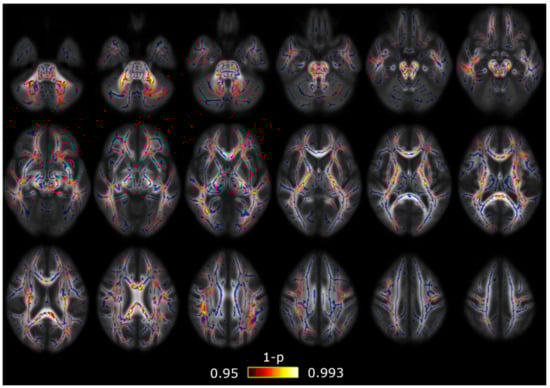

3.2. TBSS with Covariates

3.3. Correlation Analysis